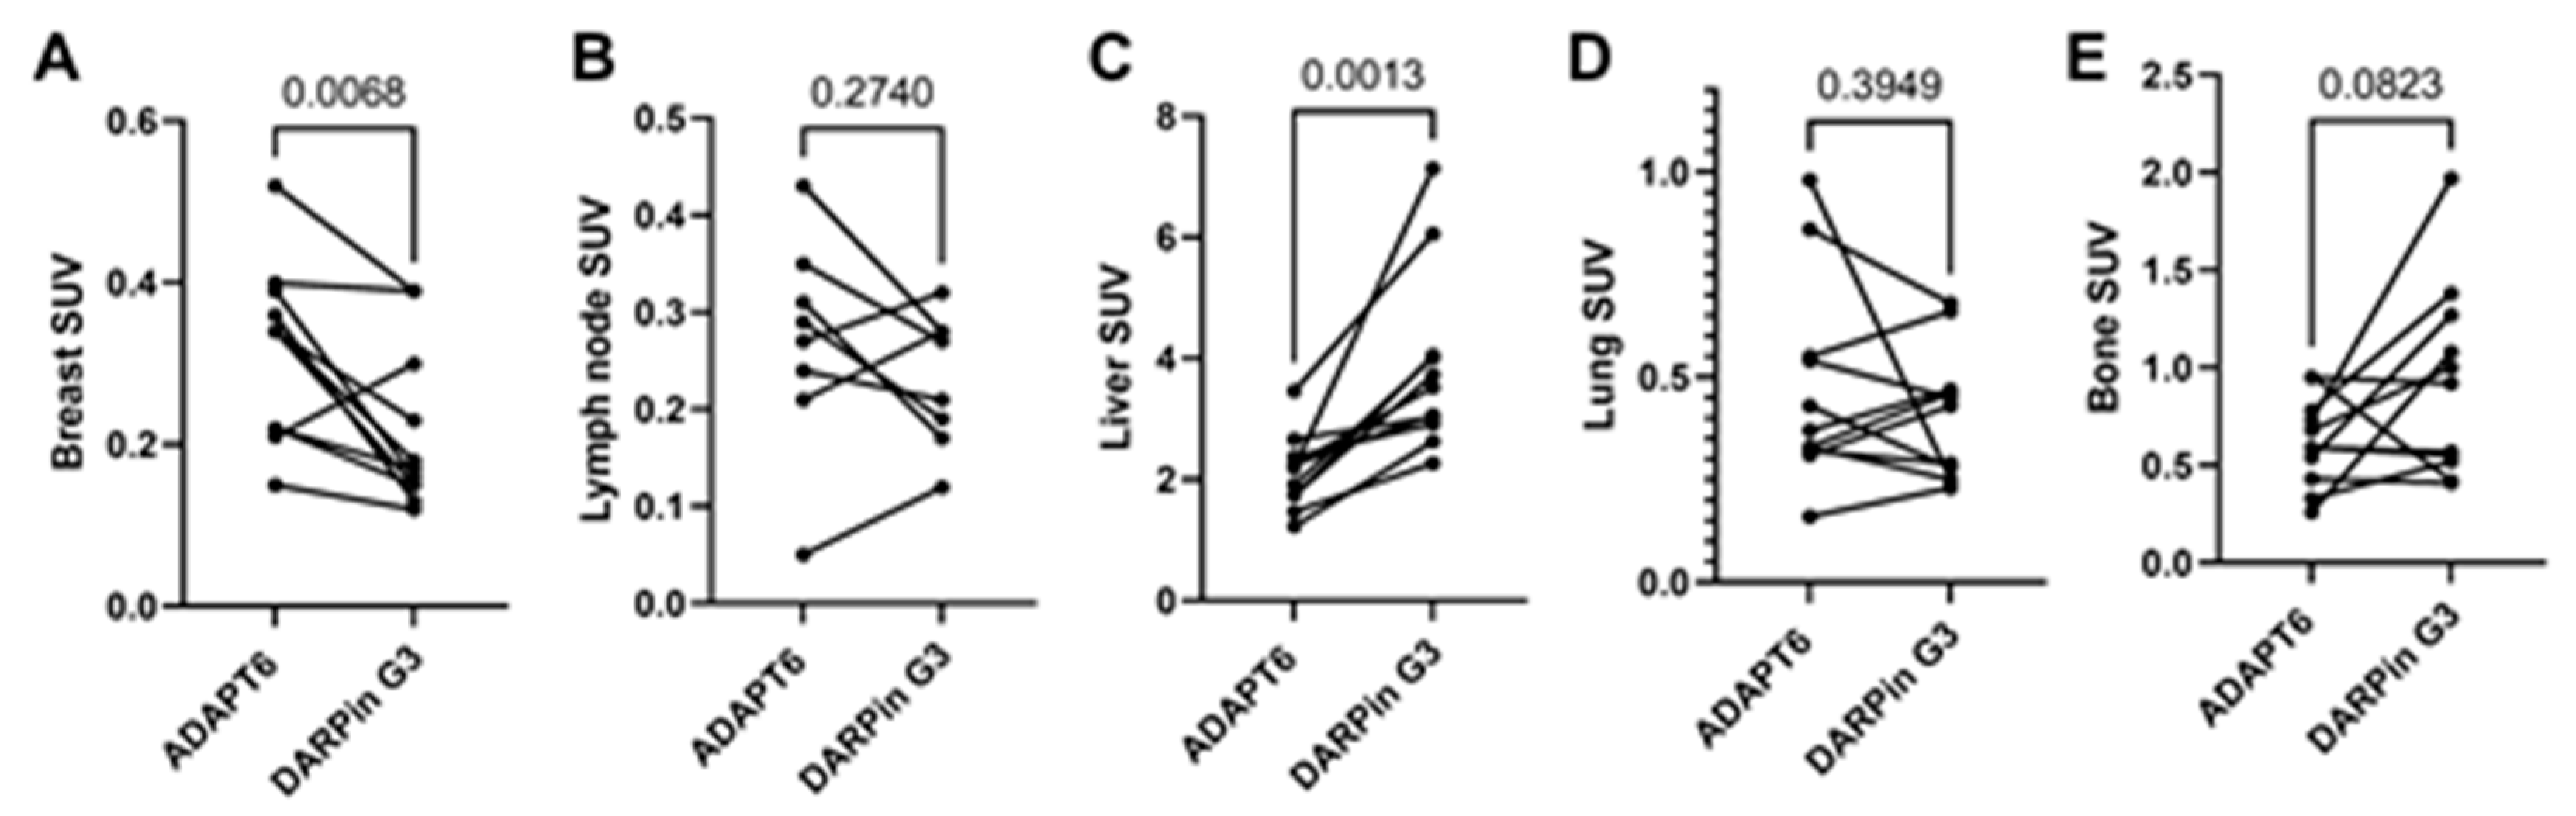

3. Results

4. Discussion